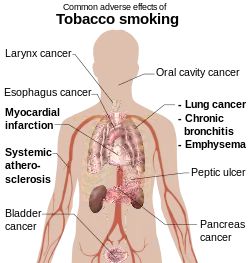

Tobacco smoking is the leading cause of preventable death and a global public health concern.[88] There are 1.3 billion tobacco users in the world, as per latest data from WHO.[17] One person dies every six seconds from a tobacco related disease.[89]

Tobacco use leads most commonly to diseases affecting the heart and lungs, with smoking being a major risk factor for heart attacks,[90][91] strokes,[92] chronic obstructive pulmonary disease (COPD),[93] idiopathic pulmonary fibrosis (IPF),[94] and emphysema.[93]

Smoking tobacco causes various types and subtypes of cancers[95] (particularly lung cancer, cancers of the oropharynx,[96] larynx,[96] and mouth,[96] esophageal and pancreatic cancer).[18] Using tobacco, especially together with alcohol, is a major risk factor for head and neck cancer. 72% of head and neck cancer cases are caused by using both alcohol and tobacco.[97] This rises to 89% when looking specifically at laryngeal cancer.[98]

Cigarette smoking increases the risk of Crohn's disease as well as the severity of the course of the disease.[99] It is also the number one cause of bladder cancer. Cigarette smoking has also been associated with sarcopenia, the age-related loss of muscle mass and strength.[100] The smoke from tobacco elicits carcinogenic effects on the tissues of the body that are exposed to the smoke.[90][101][95][102] Regular cigar smoking is known to carry serious health risks, including increased risk of developing various types and subtypes of cancers, respiratory diseases, cardiovascular diseases, cerebrovascular diseases, periodontal diseases, teeth decay and loss, and malignant diseases.[90][95][103][104]

Tobacco smoke is a complex mixture of over 7,000 toxic chemicals, 98 of which are associated with an increased risk of cardiovascular disease and 69 of which are known to be carcinogenic.[88] The most important chemicals causing cancer are those that produce DNA damage, since such damage appears to be the primary underlying cause of cancer.[105] The most carcinogenic compounds in cigarette smoke are acrolein,[106] formaldehyde,[107] acrylonitrile,[108] 1,3-butadiene,[109] acetaldehyde,[110] ethylene oxide,[111] and isoprene.[112] In addition to the aforementioned toxic chemicals, flavored tobacco contains flavorings which upon heating release toxic chemicals and carcinogens such as carbon monoxide (CO), polycyclic aromatic hydrocarbons (PAHs), furans, phenols, aldehydes (such as acrolein), and acids, in addition to nitrogenous carcinogens, alcohols, and heavy metals, all of which are dangerous to human health.[101][113][114][115][116] A comparison of 13 common hookah flavors found that melon flavors are the most dangerous, with their smoke containing four classes of hazards in high concentrations.[116]

The World Health Organization estimates that tobacco caused 8 million deaths in 2004[17] and 100 million deaths over the 20th century.[117] Similarly, the United States Centers for Disease Control and Prevention describes tobacco use as "the single most important preventable risk to human health in developed countries and an important cause of premature death worldwide."[118] Although 70% of smokers state their intention to quit, only 3–5% are successful.[119]

The probabilities of death from lung cancer before age 75 in the United Kingdom are 0.2% for men who never smoked (0.4% for women), 5.5% for male former smokers (2.6% in women), 15.9% for current male smokers (9.5% for women) and 24.4% for male "heavy smokers" defined as smoking more than 25 cigarettes per day (18.5% for women).[120] Tobacco smoke can combine with other carcinogens present within the environment to produce elevated degrees of lung cancer.

The risk of lung cancer decreases almost from the first day someone quits smoking, and it drops by 50% after 10 years of smoking cessation.[17] Healthy cells that have escaped mutations grow and replace the damaged ones in the lungs. In the research dated December 2019, 40% of cells in former smokers resembled those of individuals who had never smoked.[121]